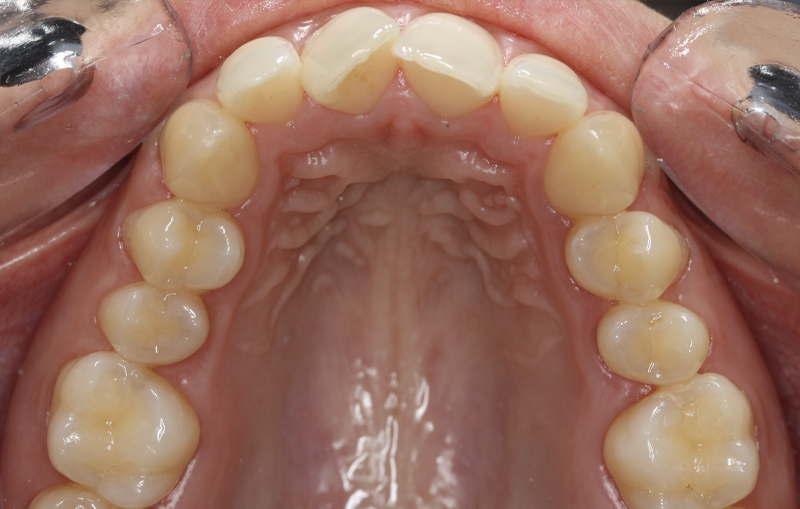

Fotografe a sua Boca de acordo com os exemplos abaixo demonstrados